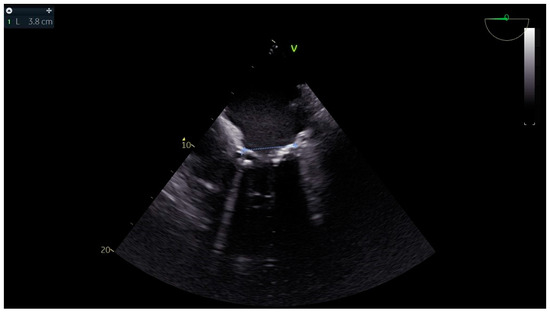

Advanced hemodynamic monitoring as per local protocol was applied with cannulation of the right radial and femoral arteries as well as establishment of peripheral access with two (wide) 16 G cannulae. Baseline invasive blood pressure before induction was 145/60 mmHg. Induction to anesthesia was uneventful without any signs of hemodynamic instability, using balanced anesthetics for the maintenance of general anesthesia too. A central line and pulmonary artery catheter were placed in the right internal jugular vein. Continuous cardiac monitoring and cerebral oximetry monitoring were applied while depth of anesthesia was monitored with the Bispectral Index. Intraoperative transesophageal echocardiography (TEE) was used and confirmed the findings of TTE, especially with a heavily calcified mitral valve annulus (Figure 1). Standard bicaval extracorporeal circulation through sternotomy and mild systemic hypothermia (32 °C) were used. Myocardial protection was made by a combination of antegrade and retrograde cold hyperkalemic blood cardioplegia. Cardiopulmonary bypass time was nearly two hours. The separation from cardiopulmonary bypass was initially smooth with minimal vasopressor support (blood pressure > 85–90/45 mmHg). A few minutes after the protamine administration an episode of profound hypotension caused major hemodynamic instability (blood pressure > 55–60/35 mmHg), which was related to the protamine side effects. However, since it persisted, regardless of the treatment with vasopressors, a thorough reassessment with the TEE was performed. This dynamic investigation revealed an obvious flap fluctuating in the left atrium, suggestive of a dissection flap in the chamber (Figure 2). (The dissection flap size was at least 7.2 cm. There was difficulty in the precise measurement of its dimension because the left atrium roof could not be visualized.) Otherwise, the two new prosthetic valves were well seated without any residual regurgitation (Figure 3 and Figure 4). The most plausible explanation for the presence of the dissection flap was the earnest mitral valve replacement performed in the setting of extensive mitral annular calcification. Hemodynamic stability was achieved with boluses of vasopressors (phenylephrine) and noradrenaline and adrenaline infusions. Since the patient was relatively stabilized under this support, the chest was closed and he was taken to the intensive care unit with a target for systolic blood pressure less than 100–120 mmHg for the first twenty-four hours (Table 1).

Figure 3. Color flow Doppler showing a competent prosthetic mitral valve in place with dissection flap in the left atrium.